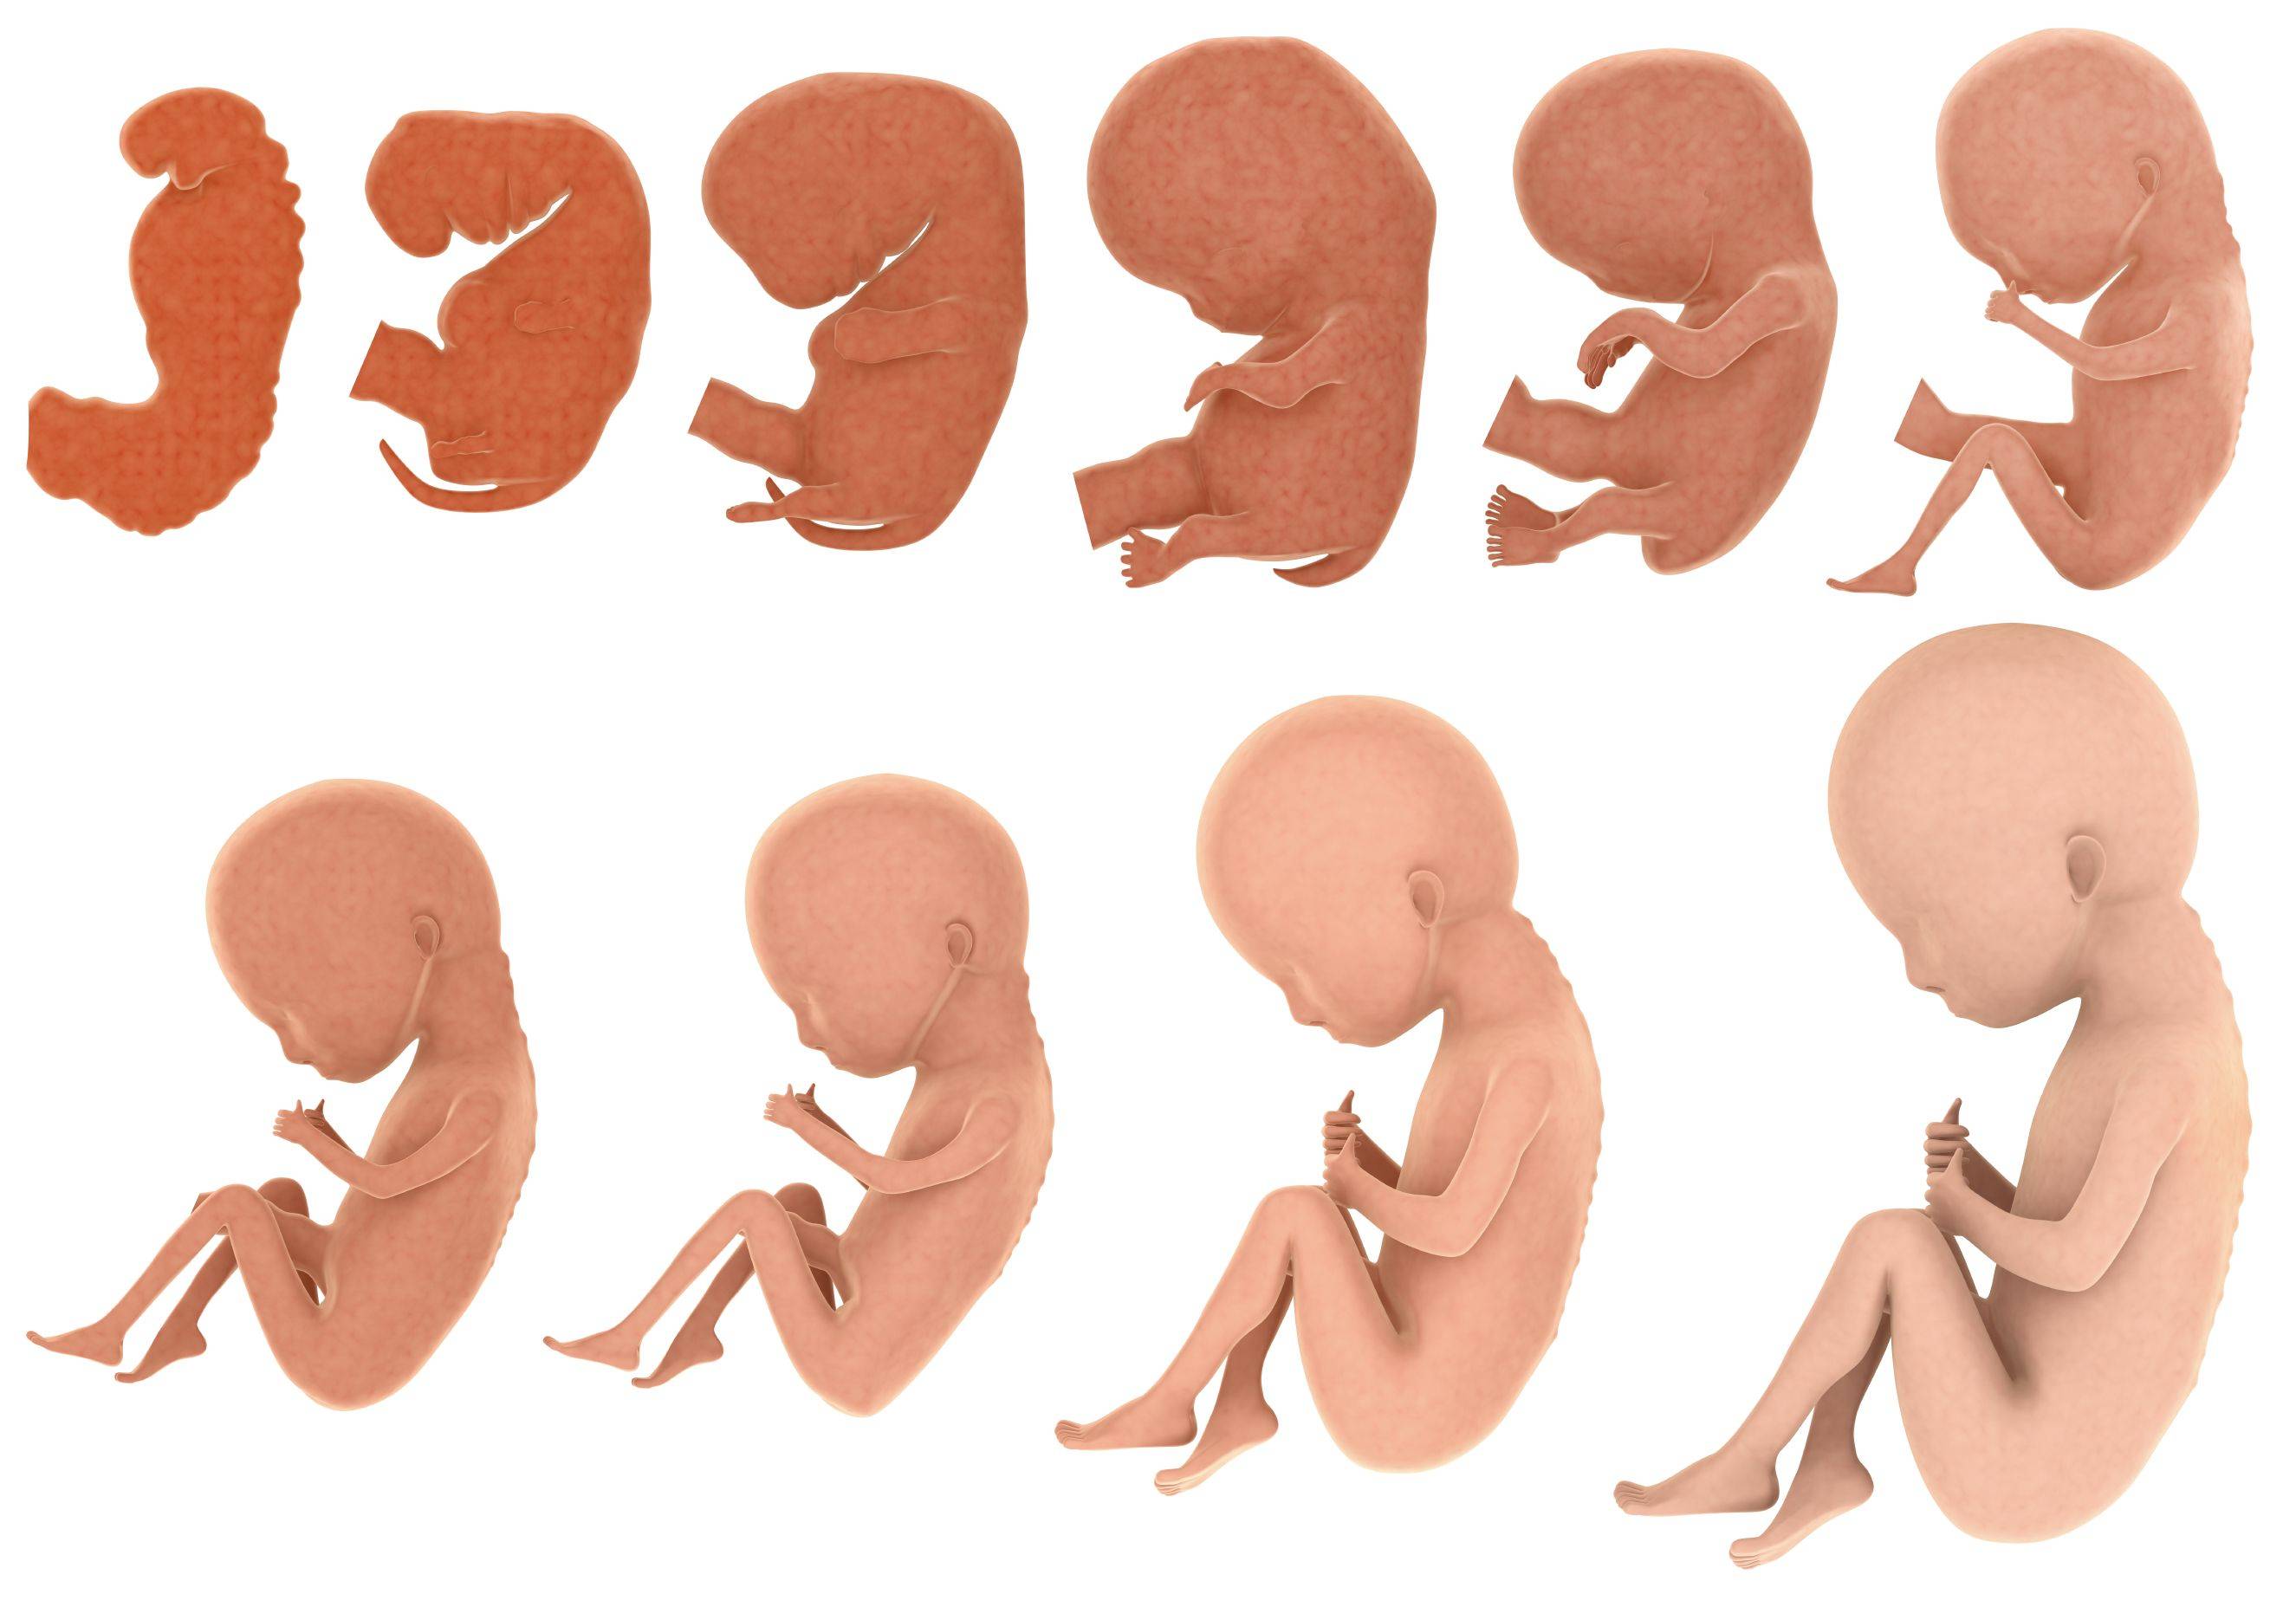

Загадочные образы животных в утробе матери